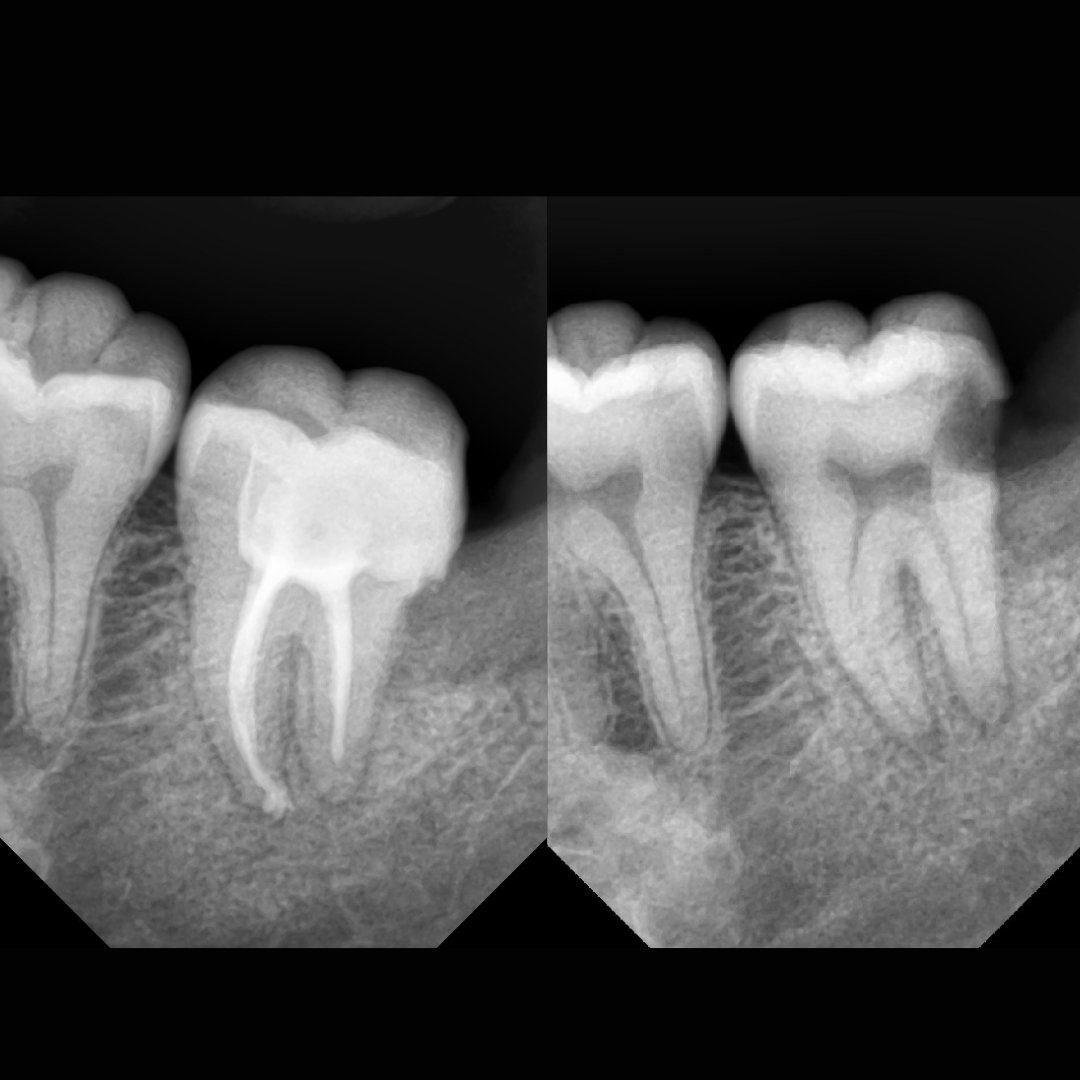

Before After Perawatan Saluran Akar (PSA) di Klinik Utama Pondok Gigi Jakarta

Transformasi nyata setelah perawatan saluran akar (PSA) di Klinik Utama Pondok Gigi Jakarta. Dari gigi rusak dan nyeri hingga kembali sehat dan berfungsi normal. Dikerjakan oleh dokter gigi profesional dengan teknik endodontik modern dan alat berteknologi tinggi untuk hasil maksimal.